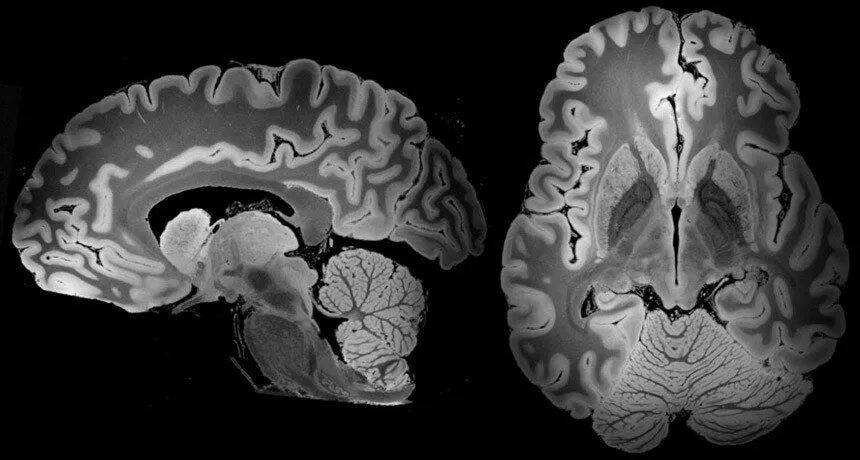

Мрт диффузия всего тела